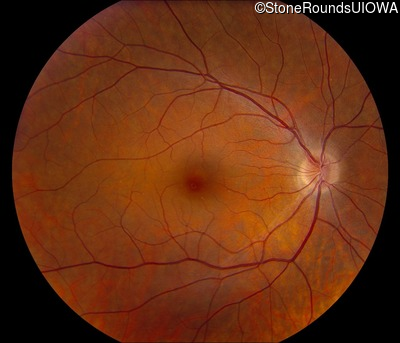

AD CSNB (IA2fii)

AD CSNB (IA2fii)

History

This 44 year old woman has had very poor vision in dim light for her entire life. She vividly remembers running into a picnic table on a bicycle in a campground as a child.